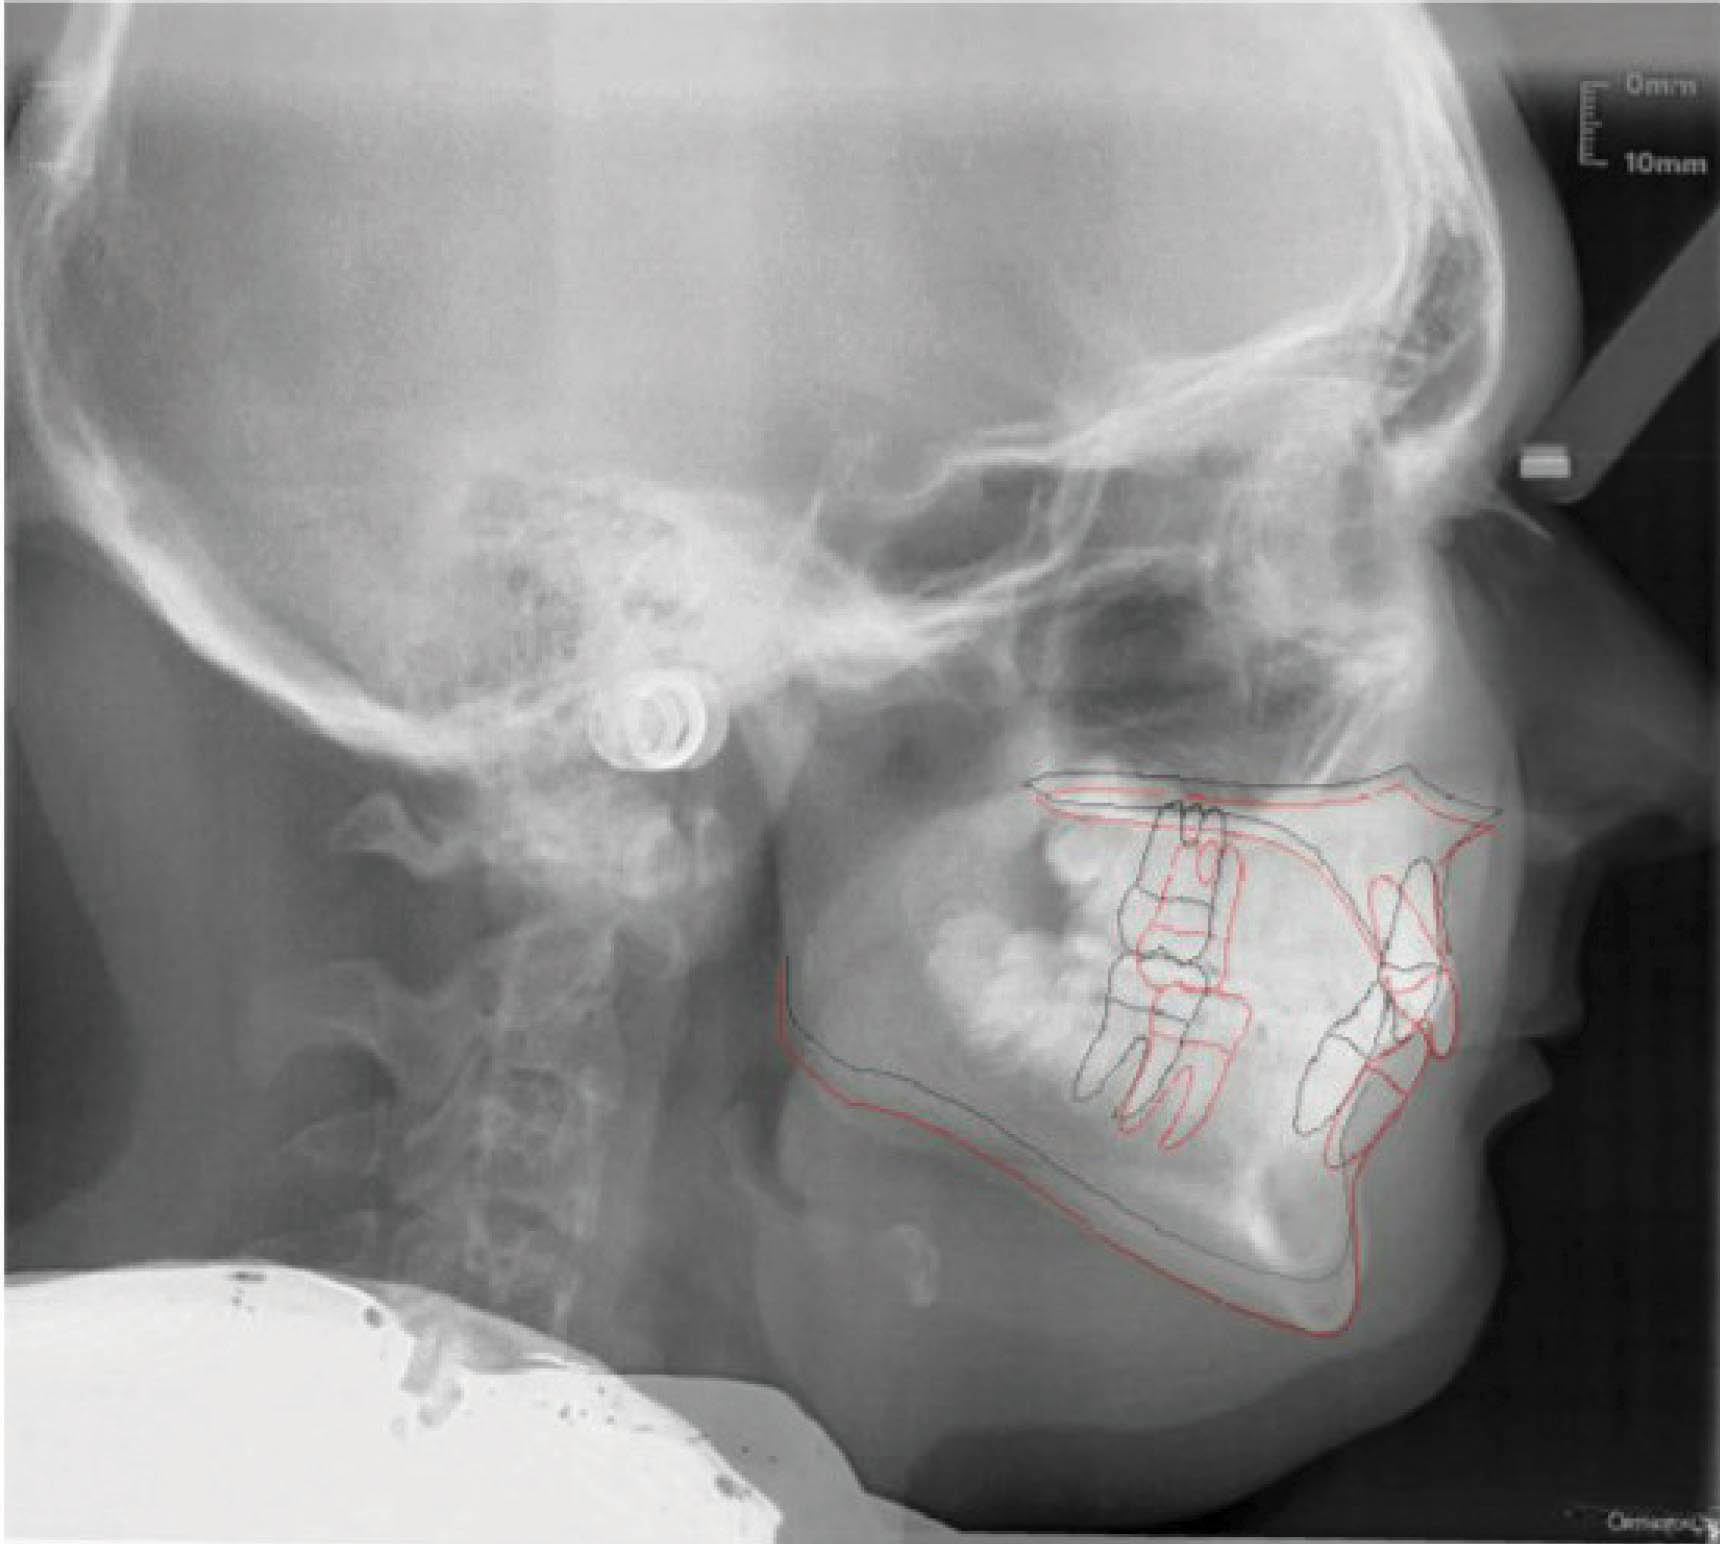

بیمارClII/2 با دیپ بایت شدید و ارتفاع عمودی کم صورت است (شکلهای 73-6 الی 75-6).

شکل 73-6

شکل 74-6

شکل 75-6

در چک لیست درمان مشاهده میکنید که انسیزورهای رترود شده بالا نیاز به اینتروژن نسبی (به کمک پروترود شدن) دارند، در حالیکه انسیزورهای پایین نیاز به اینترود شدن مطلق دارند تا کرو اسپی صاف بشود. علاوه بر این، نیاز به اکستروژن خلف هم داریم تا ارتفاع عمودی صورت بیشتر گردد. از بایت پلیتهای قدامی برای حذف نیروهای اکلوزالی (که مانع اصلاح دیپ بایت و اکستروژن خلف است) استفاده نمودیم.

میزان نمایش لبه انسیزال میزان نمایش لثه مارجین لثه قوس لبخند

دیپ بایت: اینتروژن قدام بالا پایین اکستروژن خلف بالا پایین

اپن بایت: اکستروژن قدام بالا پایین اینتروژن خلف بالا پایین

اکستروژن یا اینتروژن نسبی انسیزور های بالا مطلق انسیزور های های پایین

دیپ بایت و رابطه ClII/2 به کمک الاستیک کلاسII در طی ۴۰ ماه درمان گردید (شکل 76-6 الی 78-6). برای نحوه درمان روابط افقی به مبحث بُعد افقی مراجعه کنید